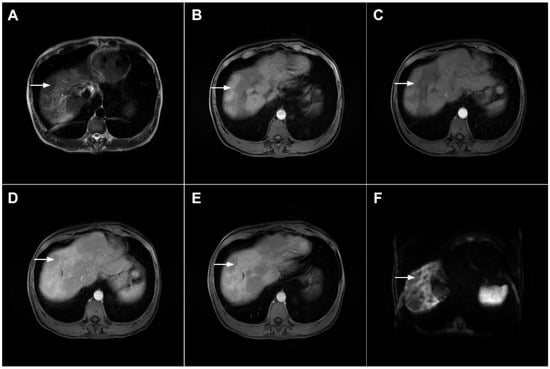

Besides the typical imaging presentation of mICC, atypical appearance can also be observed in imaging studies [24]. Hypervascular mICCs are usually small lesions and this vascular behavior might be explained by less intralesional fibrosis and abundant vascular stroma [25]. The incidence of hypervascular mICC ranges from 12.5% up to 47% in previous reports [18,25]. Since hypervascular mICCs are frequently seen in cirrhotic livers, the differential diagnosis with HCC may be very difficult. In this regard, the absence of washout and the presence of progressive enhancement together with the lack of fibrous pseudocapsule favor the diagnosis of mICC over HCC [25]. However, if hypervascular mICC shows washout in the portal venous phase, preoperative differential diagnosis with HCC is hardly possible (Figure 6). In such cases, additional findings, such as cloud appearance in the hepatobiliary phase, multiplicity around the main tumor, or intrahepatic metastasis, capsule retraction and tumor markers may be helpful for differentiating between these tumors [18,19]. Hypervascular mICC differs from typical hypovascular mICC not only in terms of vascularity but also in patient outcome, as it has been shown that the former has much better prognosis [12]. Therefore, the assessment of tumor vascularity on preoperative imaging could represent an important marker for predicting malignant characteristics in mICC [26].

Figure 6.

Hypervascular mass-forming cholangiocarcinoma in a 63-year-old woman. The axial T2-weighted image (A) shows a moderately hyperintense tumor (arrow) located in liver segments VI and VII with a subtle medial capsular retraction. The lesion (arrow) is hypointense on the plain T1-weighted image (B), hypervascular in the arterial phase (C) with washout on the portal venous phase (D). The tumor (arrow) is hyperintense on DWI (E). Hematoxylin and eosin (H&E) staining (F) showed well-differentiated cholangiocarcinoma (arrow) surrounded by normal liver parenchyma (dashed arrow); original magnification ×40.

Mucinous cholangiocarcinoma is a rare variant of mICC characterized by rich mucin production [24,27]. According to previous studies, mucinous mICC originate from mucin-producing cholangiocytes located in large bile ducts [28]. Imaging findings in mucinous mICC reflect characteristic histopathological features of the lesion with cancer cell nests suspended in a large mucinous lake [29]. Therefore, these lesions display strong T2-weighted hyperintensity [27]. Moreover, as cancer cells in the center of the lesion are scarce, these tumors show only slight progressive enhancement of intralesional septa and cellular nests in postcontrast studies (Figure 7) [27]. Due to its very high signal intensity on T2-weighted images and centripetal pattern of enhancement, mucinous mICC may be misdiagnosed as hemangiomas [29]. Concerning similarities in the postcontrast behavior of mucinous mICC and hemangiomas, it should be kept in mind that mICC displays continuous ragged rim enhancements in contrast to the discontinuous, stronger peripheral and centripetal enhancement following the blood pool seen in hemangiomas [24,29].

Figure 7.

Mucin-rich mass-forming cholangiocarcinoma in a 78-year-old woman. The axial T2-weighted image (A) shows the lobulated hyperintense lesion (arrow) located in the subcapsular region of liver segment IVB, which is associated with capsular retraction. On the plain T1-weighted image (B) the lesion (arrow) is hypointense. In the arterial phase (C), ring enhancement can be seen with slight “ragged” central enhancement in the portal venous (D) and delayed phase (E). On DWI, diffusion restriction is noted on the periphery of the lesion (arrow) while no restriction is seen in the central part of the tumor (F). Corresponding ADC map showing targetoid appearance of the lesion is shown on (G). Hematoxylin and eosin (H&E) staining (H) showed cholangiocarcinoma (arrows) adjacent to normal liver parenchyma (dashed arrow); original magnification ×40.